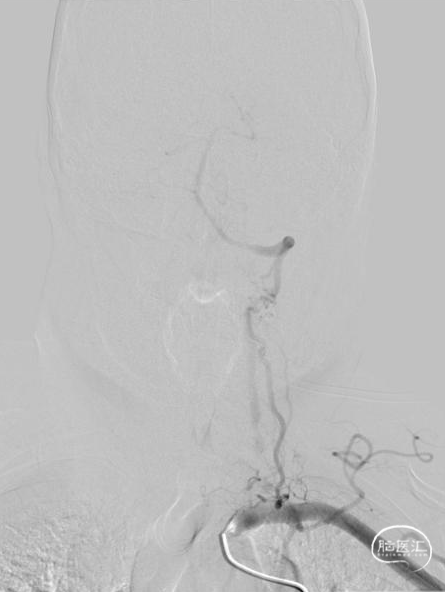

➢头颈部CTA(三维重建MIP像)

➢头颈部CTA(原始像)

该患者术前影像学提示右椎纤细、V4段未汇入基底动脉,考虑孤立椎。且左椎开口存在重度狭窄,左椎V4存在局部重度狭窄可能,故该患者存在血管内介入治疗指征,排除禁忌症后拟行“全脑血管造影术+左侧椎动脉开口血管成形术”。

术前影像考虑右侧孤立椎,左侧椎动脉V1段重度狭窄、狭窄段以远扭曲成襻且合并长节段多发动脉粥样硬化狭窄改变(夹层待排),同时左椎V4段局部重度狭窄可能;

术中造影证实右椎纤细、右椎V4段可见微弱血流入基底动脉、左椎动脉开口闭塞、颈升动脉通过侧支循环向左椎V3供血并逆流至V1中段、左椎V4轻度狭窄;